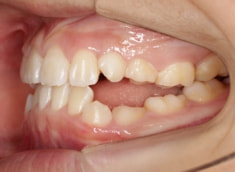

治療前